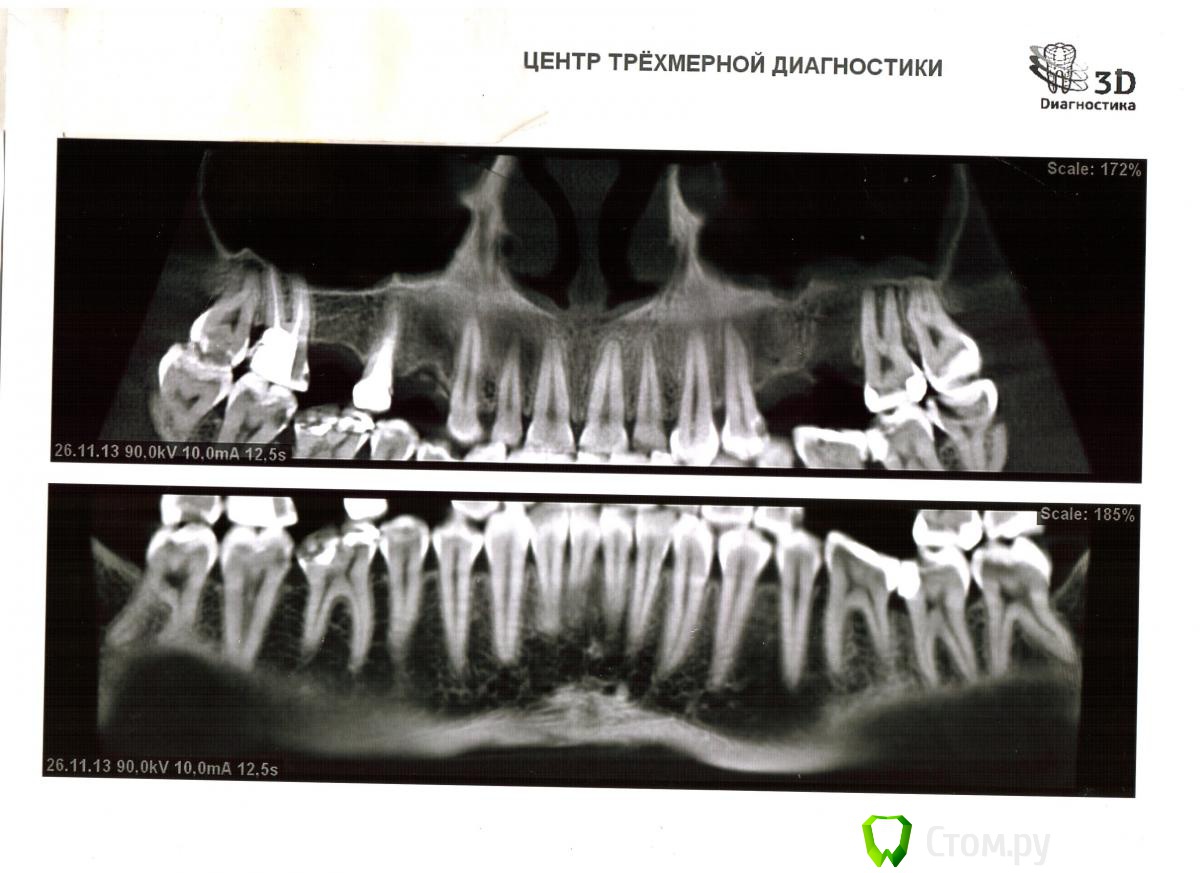

agni Опубликовано 17 декабря, 2013 Поделиться Опубликовано 17 декабря, 2013 Уважаемые стоматологи помогите разобраться с планом лечение зубов.27 недавно вылечила с удалением нервов. ( Болел) Сегодня предстоит имплантация зубов 26,25. Что стоит лечить в самую первую очередь? Стоит ли удалять 48,38? Ссылка на комментарий

x3m Опубликовано 19 декабря, 2013 Поделиться Опубликовано 19 декабря, 2013 поясняю. снимок в формате среза одной плоскости, малоинформативен.лучше выложить ортопантомограмму 16,14 - имплантация.15 - прицельный снимок.17 - ВКВ+коронка (?)18 - похоже на очаг воспаления на корне (?)18,38,48 - кариес (?)47 - кариес, 46 - контроль пломбыконтроль 36,37 - несостоятельные пломбы (?)если удалять восьмерки - тогда все 4. Ссылка на комментарий